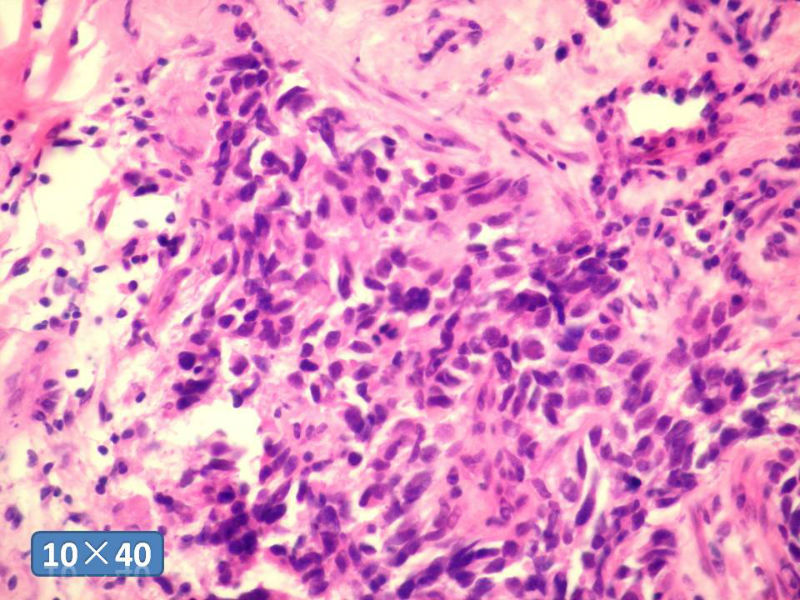

女性,50岁,乳腺肿物,冰冻切片(图1-25)

HE